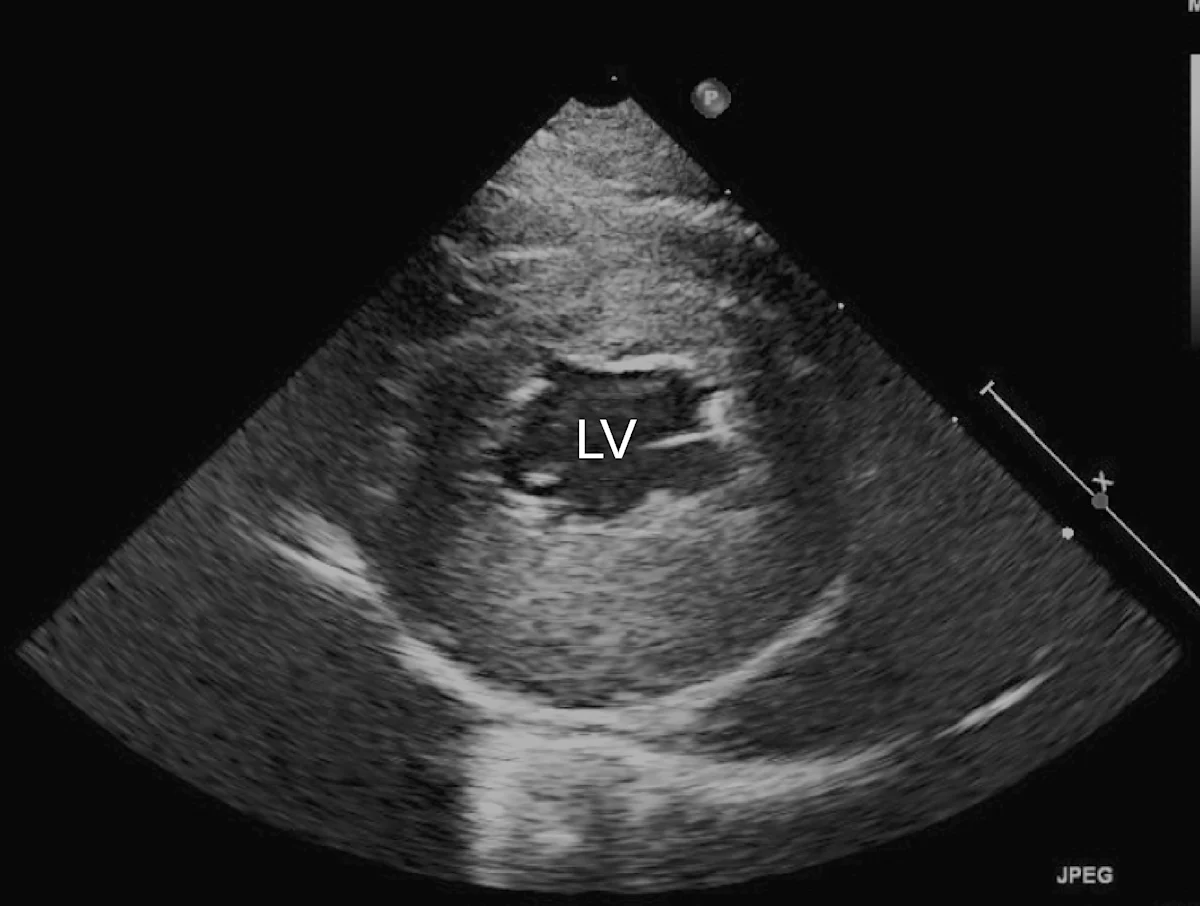

Marked left atrial enlargement was present on echocardiography after stabilization and pain management (see Treatment). A formed thrombus was apparent within the left auricle (Figure 4) and spontaneous echo contrast or smoke was present within the left atrium (Figure 5). This spontaneous echo contrast is often seen with marked chamber dilation and blood stasis; although its presence is associated with an increased risk for thrombus formation, it is not a result of a formed thrombus. Thickening of the left ventricular walls was also noted (Figure 6), which is consistent with underlying hypertrophic cardiomyopathy.

Right parasternal short-axis echocardiographic view of the left ventricle (LV) showing concentric hypertrophy, particularly of the posterior ventricular wall